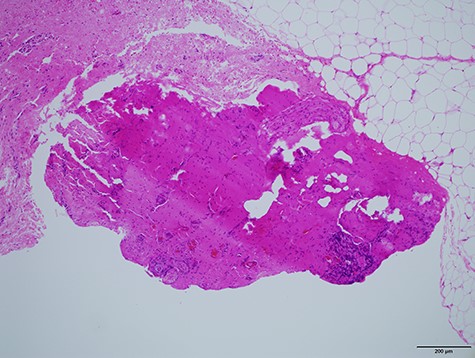

Histologically (Fig. 10), fibrosis and inflammatory granulation were seen. Inflammatory reaction of lymph nodes was observed. Epithelial cells could not be found in the slices.

Histological specimen of the final surgery. Inflammatory reaction of a lymph node inside of parotid the parotid gland was observed.

Histologically, no epithelial cells nor lumen was identified inside of it. The epithelial structure was presumed to have been small and escaped from the slices for histology.